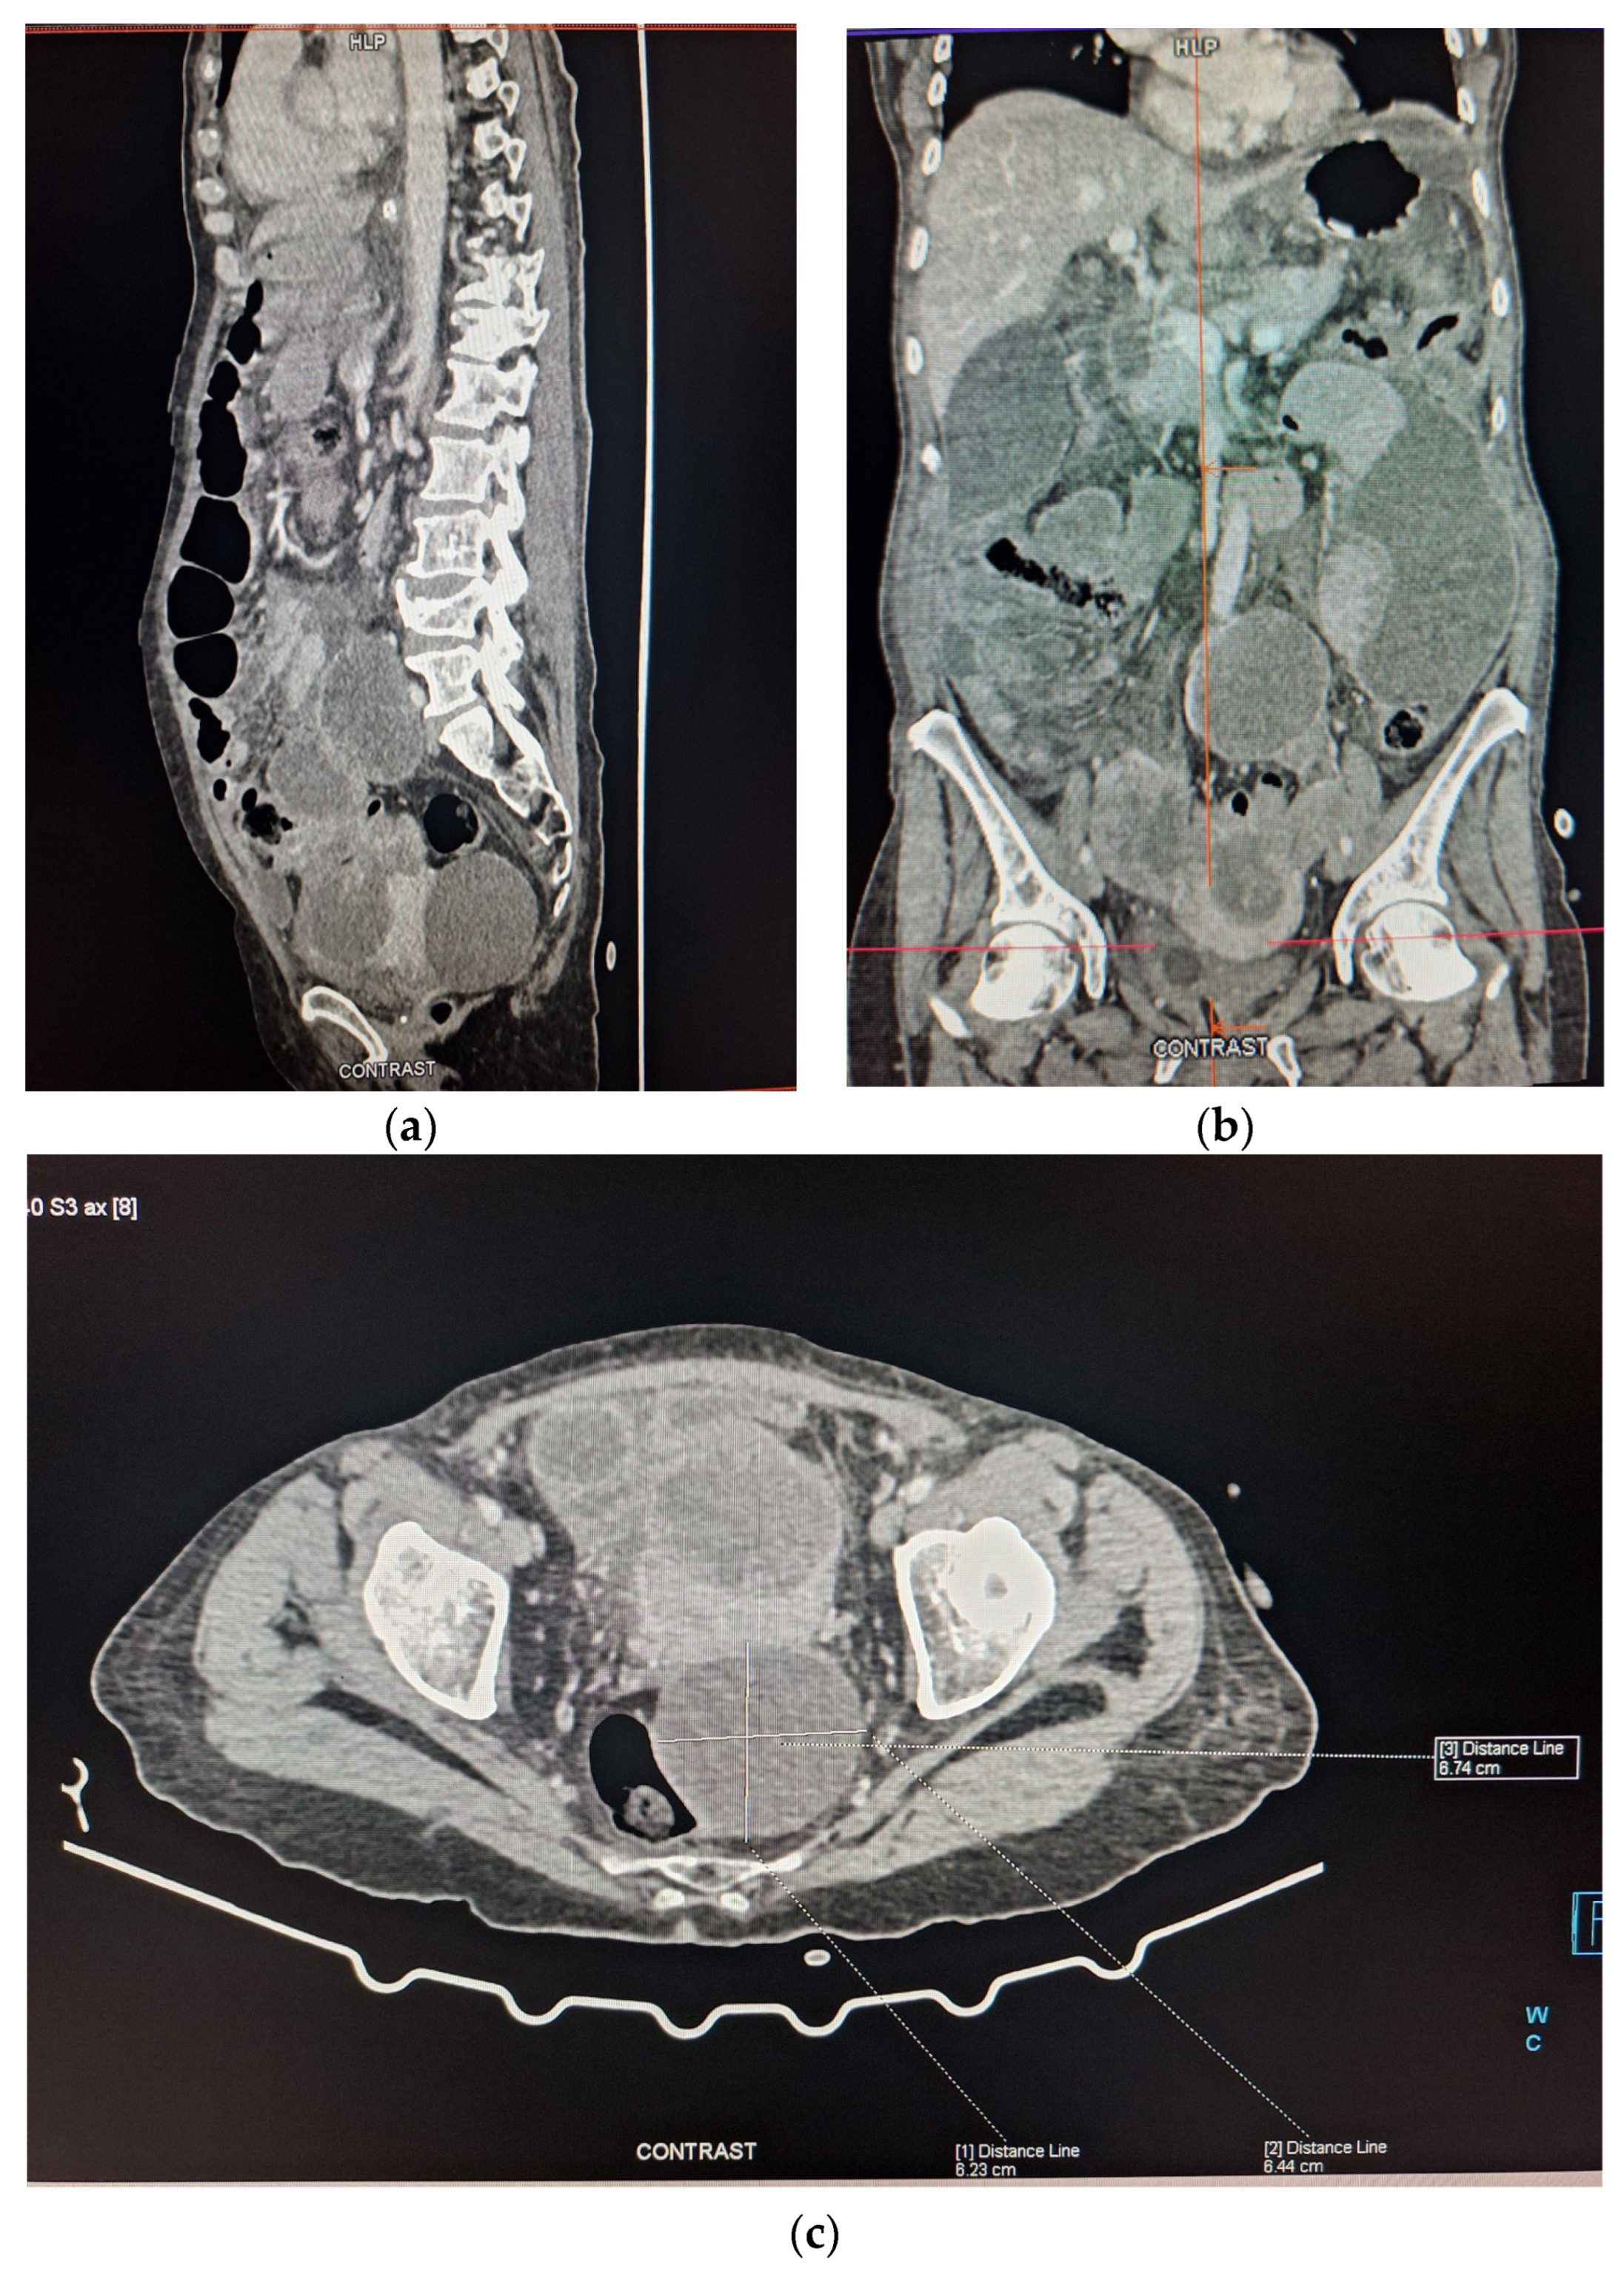

The patient was admitted to the Surgical Ward and underwent a Computered Tomography (CT) scan, with oral Gastrografin contrast, which revealed two abscess cavities - one below the right hemidiaphragm and one in the left paracolic gutter, generalized distension of her small bowel, a large cystic mass in the right ovary and multiple peritoneal implants (Figure 1a–c). Due to the presence of peritoneal implants a preliminary diagnosis of ovarian cancer with generalized peritoneal carcinomatosis was made. Initial treatment was conservative, consisting of intravenous fluids, a nasogastric tube and antibiotics. Two days later, with no improvement in the patient’s clinical condition, a second abdominal CT scan was performed, again demonstrating distended small bowel loops with no distal contrast passage. Following discussions with the patient and her family, and consultations among the medical, surgical and gynecological teams, the following day, the decision was made to proceed with a laparotomy the following day.

Figure 1. A contrast enhanced abdominal CT-scan of the patient. (a) The cystic mass and the small bowel dilation are identified. (b) Two abscess cavities are identified, one below the right hemidiaphragm and one in the left paracolic gutter. (c) The cystic mass is identified with a maximum diameter of 6.74 cm.